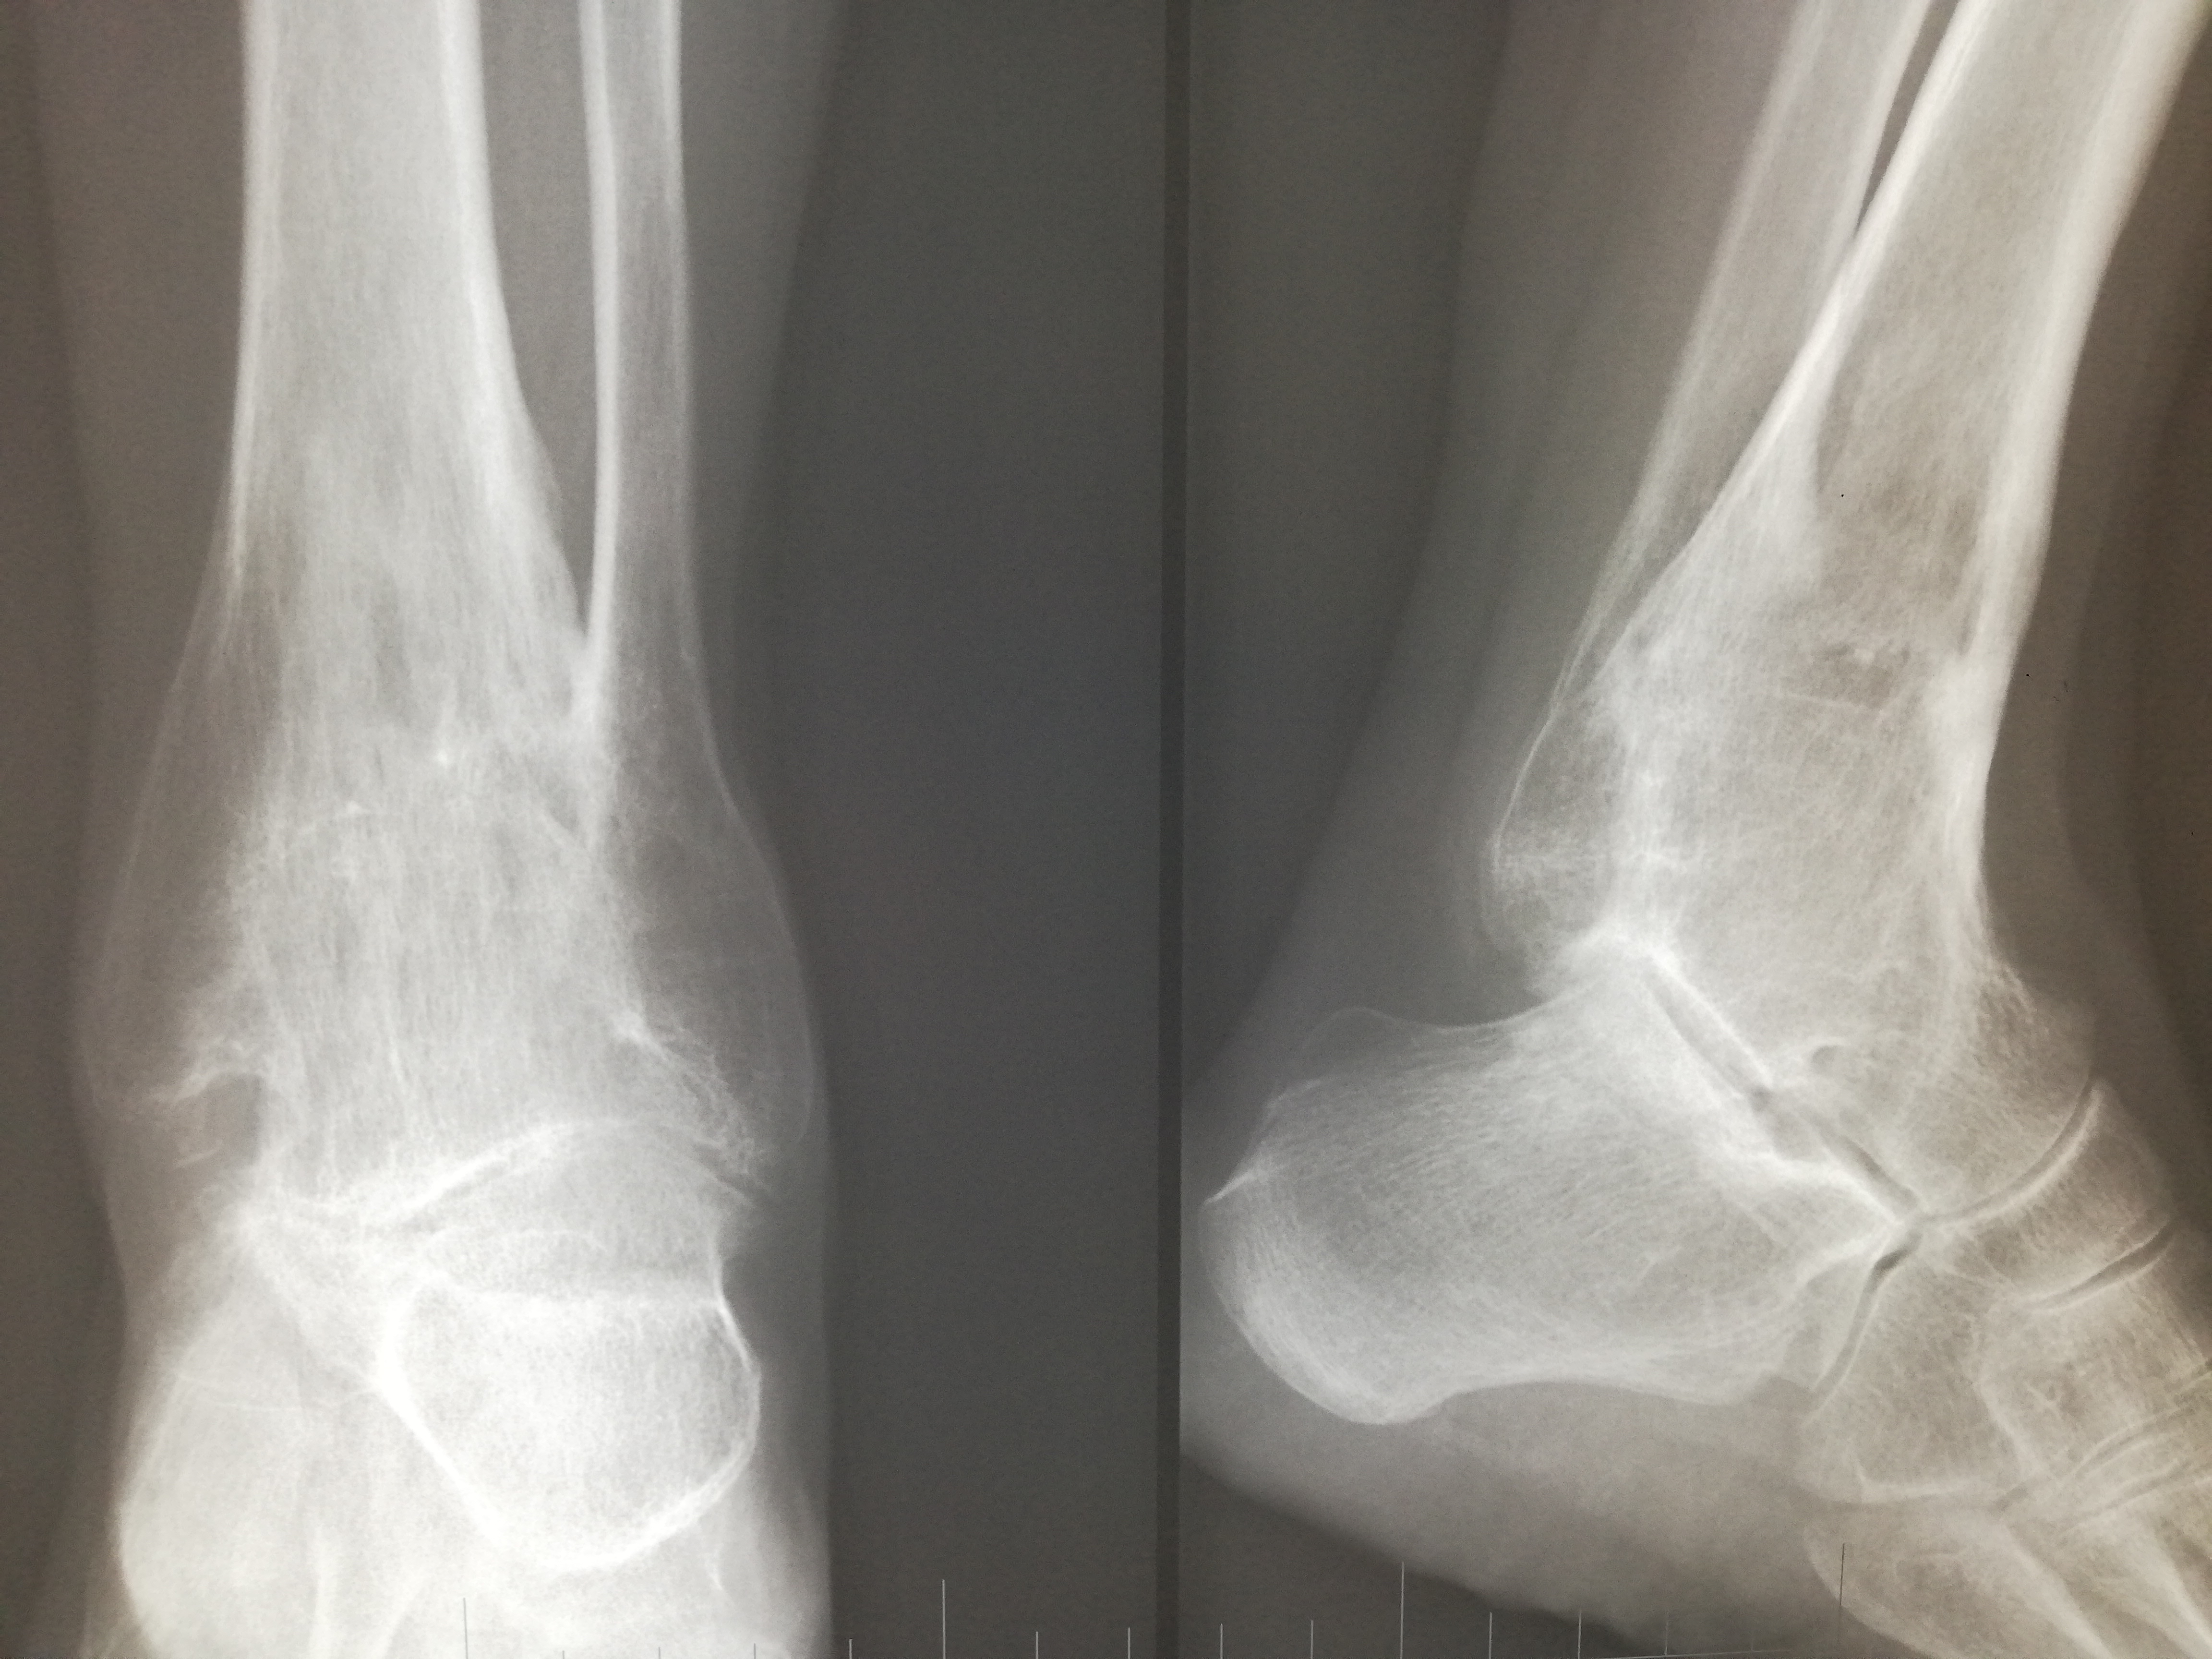

Рентгеновские снимки анкилоза суставов: Как это выглядит